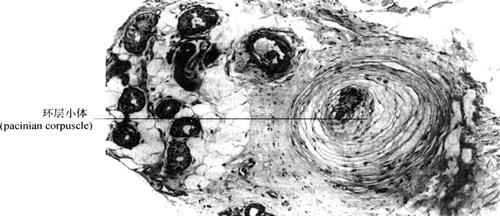

(2)有被囊神经末梢(encapsulated nerve ending):外包裹有结缔组织被囊,常见的有如下几种:①触觉小体(tactile corpuscle):分布在皮肤真皮乳头内,多呈卵圆形,小体内有横列的扁平细胞,外包有结缔组织囊,有髓神经纤维进入小体时失去髓鞘,其分支盘绕在扁平细胞间,可感受触觉(图2-56)。②环层小体(paciniancorpuscle):分布于皮肤的皮下组织、肠系膜等处,呈圆形或卵圆形,体积较大,被囊是由数十层呈同心圆排列的扁平细胞组成,中央有一均质状圆柱体,有髓神经纤维失去髓鞘后穿入其中,可感受压觉和振动觉(图2-57)。③肌梭(muscle spindle):分布于骨骼肌内的梭形小体,外有结缔组织被囊,内含若干条细小骨骼肌纤维,称梭内肌纤维。感觉神经纤维的末端,进入结缔组织被囊后失去髓鞘缠绕在每条梭内肌上,主要感受肌纤维的伸缩变化(图2-58)。

图2-57 环层小体(400×)